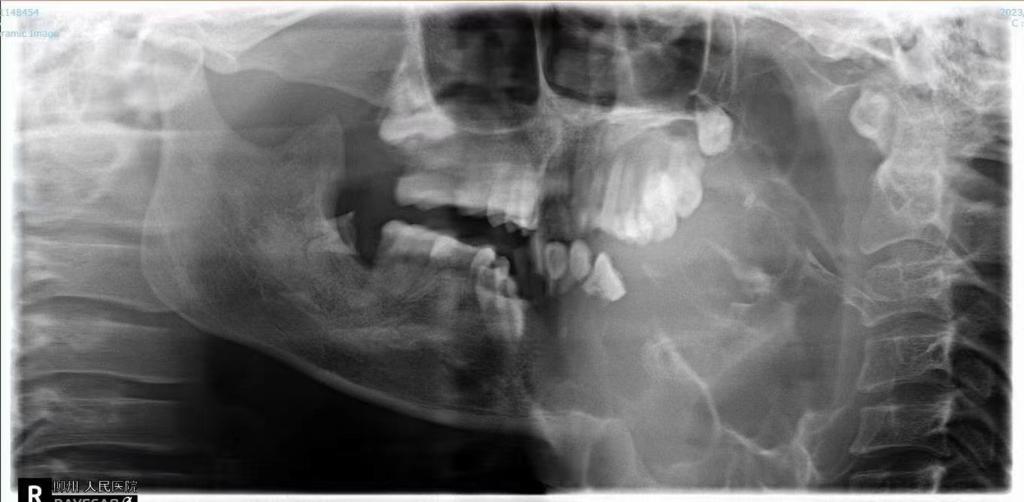

無奈之下,近日,劉女士在家人的陪同下來到了柳州市人民醫院口腔科就診。接診的副主任醫師劉彥杰看到患者情況后也有些吃驚,這是他從醫多年見過的最大的下頜骨腫瘤。經檢查發現,腫瘤已經完全侵犯患者左邊下頜骨,口腔內還有一大塊腫瘤暴露,左下牙已經完全被腫瘤侵犯消失,腫瘤很容易出血,上頜骨也被腫瘤壓迫變形。好在腫瘤表面皮膚還比較完整,可以用來做術后口腔缺損的修復。

▲術前術后對比

術后,經過醫護團隊的精心治療與管理,劉女士恢復良好。從她的臉正面照來看,左右兩側基本對稱。半年后便可以做腓骨游離皮瓣重建其下頜骨,種植牙修復缺牙,便可恢復面型及咬合功能,過上正常的生活。